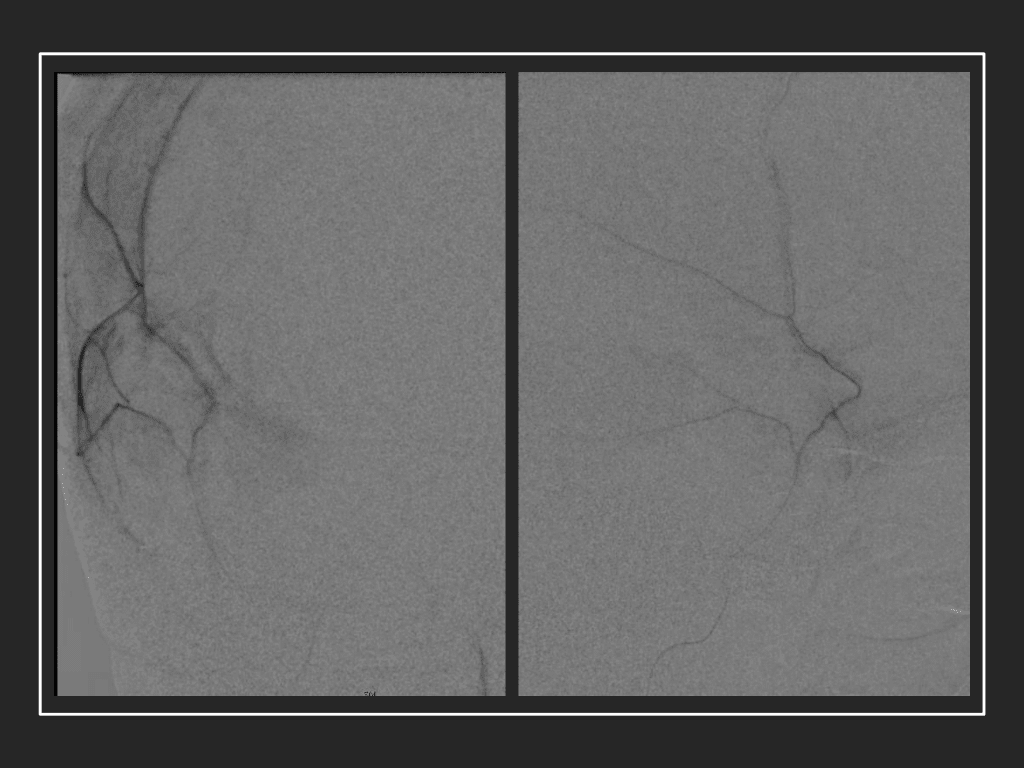

Figure 7. Neovascularized membranes within cSDH

Although conventional surgical methods, such as burr hole irrigation or observation in asymptomatic or minimally symptomatic patients have been the mainstay of treatment, middle meningeal artery (MMA) embolization has emerged as a promising adjunctive or alternative treatment. MMA embolization is a neuroendovascular technique which involves placing a microcatheter into the Middle Meningeal Artery, most commonly on the side of the cSDH (occasionally, bilateral embolization has been recommended for larger or bilateral collection. Embolization of both the anterior (frontal) and posterior (parietal) division is performed using a variety of embolic materials (liquid NBCA, Onyx, coils), although polyvinyl alcohol particles of <250 microns are most commonly used to achieve distal penetration and occlusion of the pre-capillary and capillary beds. The micro-leakage of blood and transudative proteinaceous inflammatory fluid in these inflammatory membranes is creating an imbalance in cycle of resorption and preventing resolution or promoting recurrence or growth of these cSDH collections and associated mass effect and midline shift.